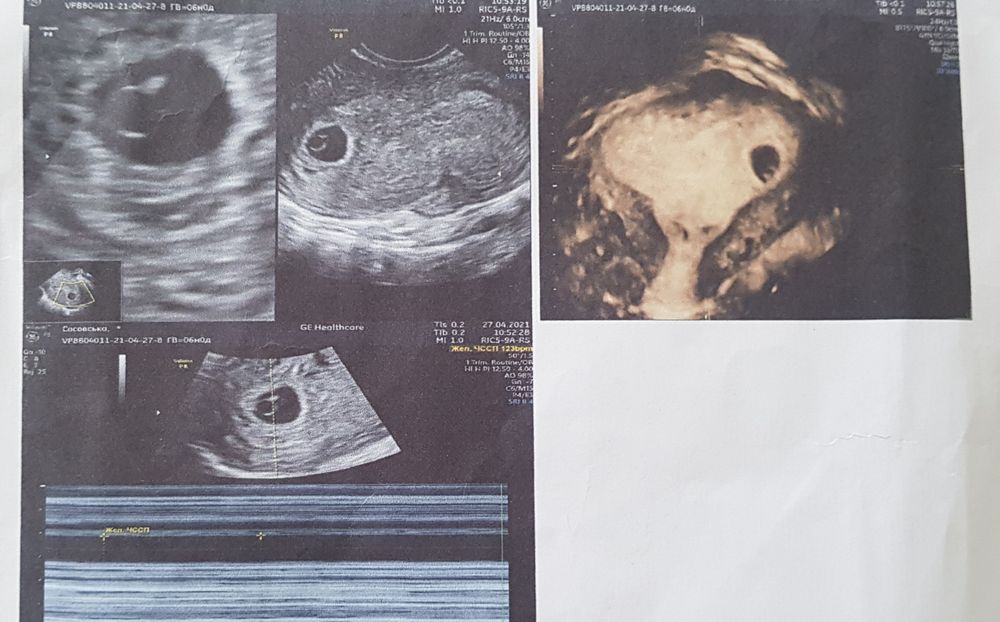

УЗИ делала вагинально оба раза. Первое фото 6 недель по М, а второе 8 недель по М. Итак, у кого какие предложения?!😅😅

вот эта белая часть вроде как хорион, он и прикрепление эмбриона по левой стороне. А при трансвагинальном узи слева это мальчик